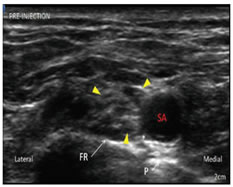

Figure 6                                                                           Figure 7

Figure 6: View on the USG screen before injection of local anesthetic drug; Figure 7: Postanesthetic injection: Right supraclavicular brachial plexus (yellow arrows)

Brachial plexus = yellow arrows. FR = first rib, SA = subclavian artery, P = pleura, * = corner pocket. Local anesthetic (dashed lines) had been deposited in corner pocket (*). Note the nerves now appeared to be floating on the injected anesthetic drug. FR = first rib, SA = subclavian artery.

Patients were positioned supine with head end elevated , head turned towards the opposite side and the arm to be blocked was kept adducted by the side of patient. Sterile painting and draping were done. USG linear probe of 7-10 MHz was used to locate the brachial plexus. After applying sterile jelly the probe was moved from cephalic to caudal direction to bring subclavian artery in the center of the screen to a point where nerve plexus was situated lateral to artery (Figure 6). A 20G 100mm Quinckie spinal needle was inserted from lateral to medial direction by using in plane technique so that needle remains visible at any point of time and injury to pleura can be prevented. Combination of Inj. Bupivacaine 0.5 % and Inj. Lidocaine 2 % was used. Total 25 ml of local anaesthetic solution was taken (15 ml of Inj. Bupivacaine and 10 ml of Inj. Lidocaine). Once the needle was between brachial plexus and artery, half of the solution of local anesthetic was injected first in corner pocket, i.e. at 7’O clock position of subclavian artery and remaining half of the local anesthetic solution was injected in the superior pocket i.e. 11’O clock position of the subclavian artery after redirecting the needle (Figure 7).